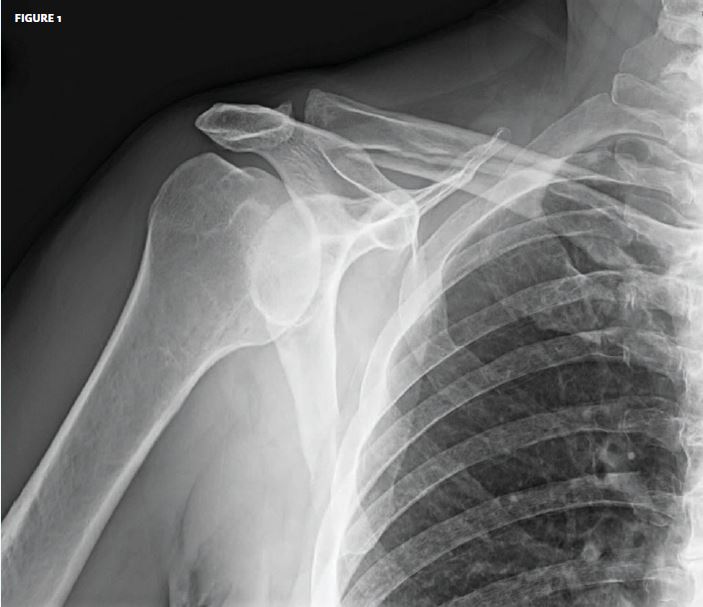

From www.jucm.com

Unable to lift arm over head Archives Journal of Urgent Care Medicine Neck Pain Unable To Lift Arm Rarely, neck pain can be a symptom of a more serious problem. Seek medical care for neck pain with numbness or loss of strength in. Symptoms of venous thoracic outlet syndrome. Cervical radiculopathy (also known as “pinched nerve”) is a condition that results in radiating pain, weakness and/or numbness. Sharp neck pain is not in itself a red flag. Pain. Neck Pain Unable To Lift Arm.